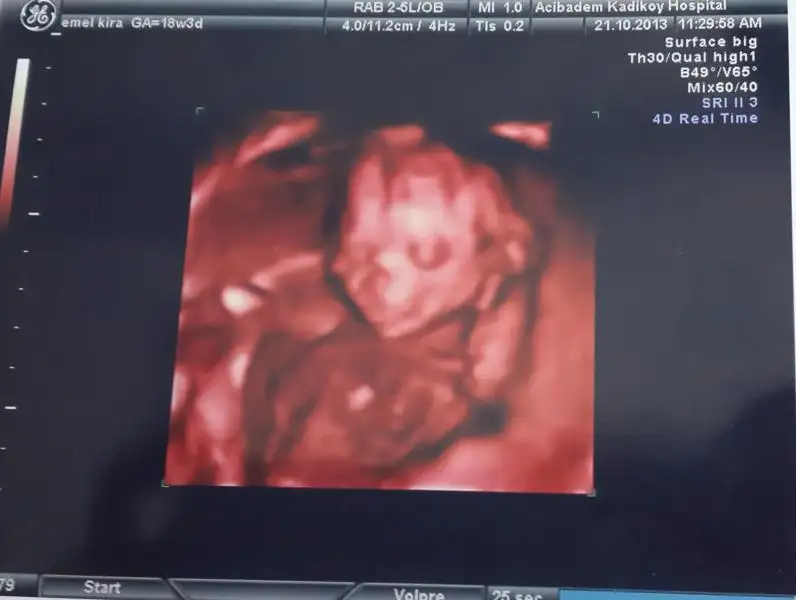

Kızlar ben dayanamıcam bebişimin 4 boyutlu fotosunu paylaşıcam:)) o kadar güzel poz veriyordu ki doktorum bu poz kaçırılmaz deyip fotosunu çekti güzel kızımın ve ultrasonda gülüyordu resmen hatta fotoda bile gülüyor gibi.. git gide annelik benliğime işliyor. Bundan bahsederken bile gözlerim doldu benim çok güzel çoookkk..